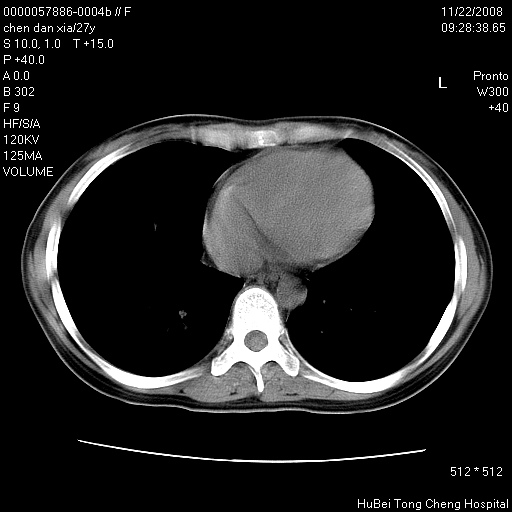

标题: CT16752:F,27Y。发热咳嗽20余天,伴盗汗。 [打印本页]

标题: CT16752:F,27Y。发热咳嗽20余天,伴盗汗。

考虑双肺粟粒性肺tb,右侧胸膜增厚.

右下肺见片絮状影,两肺野内分布不均的小结节影,结核并肺内播散可能性大,建议结合实验室检查 .

右下肺纹理模糊;纵隔可见肿大淋巴节;右心缘旁结节,边缘光滑,纵隔窗病变范围较肺窗明显小,首先考虑右下肺结核,不排外淋巴瘤

右侧前胸壁胸膜局限性肥厚(胸膜炎?)其他的强化观察.

以下是引用hyhxn在2008-11-22 18:02:00的发言:[br]考虑双肺粟粒性肺tb,右侧胸膜增厚.